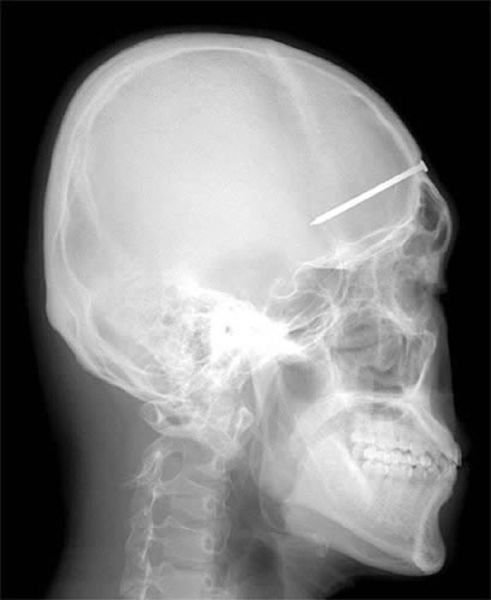

Стоматолог обнаружил источник зубной боли. Патрик Лоулер (Patrick Lawler) жаловался на боль вдоль нёба его рта: как оказалось, причиной был 10 сантиметровый гвоздь, который строитель нечаянно вставил в свой череп шестью днями ранее.![]()

По множественным сообщениям международной прессы, 11-летний китайский школьник Лю Чеонь (Liu Cheong) столкнулся со смертью, когда его друг выстрелил ему в голову 40-сантиметровой стрелой. Стрела вошла в его череп через глазницу и застряла в голове. Каким-то чудом мальчик избежал смертельной мозговой травмы.

5-сантиметровый гвоздь, который можно заметить на этом рентгеновском снимке, был обнаружен после того, как мужчина из Сеула, Южная Корея, обратился в больницу с сильной головной болью. После обследования и опроса мужчины врачи предположили, что гвоздь был результатом несчастного случая, произошедшего четыре года назад, но мужчина не заметил, что в его голове был гвоздь.![]()